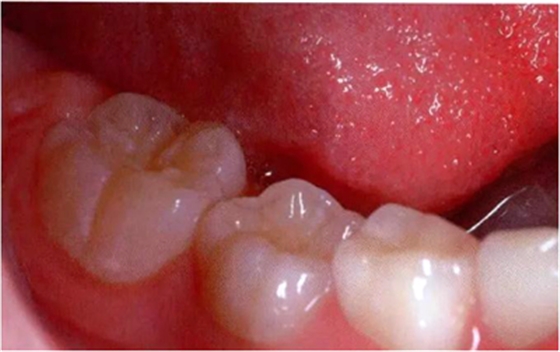

圖1:輕度下沉的臨床像